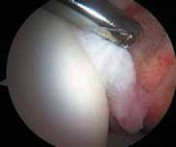

2. Disrupted fibers of the ligamentum teres, whether from trauma or degeneration, can be quite painful, creating soft tissue impingement within the joint.

Associated with this soft tissue impingement, the pulvinar tissue often is hyperplastic or fibrosed and also can create painful symptoms.

Indiscriminate débridement of the ligamentum teres should be avoided and intact fibers preserved; however, débridement of the disrupted portion can be quite beneficial ( TECH FIG 4).

Most of the contents of the acetabular fossa are best accessed from the anterior portal.

However, a portion of the posterior contents often is best accessed with instrumentation introduced from the posterolateral portal.

Between these two sites most pathologic processes can be accessed with combinations of straight, curved, and flexible instruments.

---

A B C TECH FIG 4 • A. Arthroscopic view from the anterolateral portal reveals disruption of the ligamentum teres (

). B. Débridement is begun with a synovial resector introduced from the anterior portal. C. The acetabular attachment of the ligamentum teres in the posterior aspect of the fossa is addressed from the posterolateral portal. (Reprinted with permission from Byrd JWT, Jones KS. Traumatic rupture of the ligamentum teres as a source of hip pain. Arthroscopy 2004;20:385–391.) PEARLS AND PITFALLS Patient selection Patient positioning Portal placement Avoid iatrogenic damage Avoid excessive labral resection Avoid advanced disease states